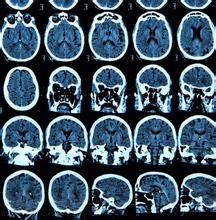

顱腦CT介紹

顱腦的CT檢查是通過CT對顱腦進行檢查的一種方法。

頭顱CT是一種檢查方便,迅速安全,無痛苦,無創傷的新的檢查方法,它能清楚的顯示顱腦不同橫斷面的解剖關係和具體的腦組織結構。因而大大提高了病變的檢出率和診斷的準確性。總體上講,CT對人體硬組織的顯像要比軟組織的更好。頭顱CT檢查對於顱內、顱骨、頭皮的大部分疾病的診斷有重要意義(包括外傷、腫瘤、炎症、血管病變、中毒、變性和代謝性疾病等)。